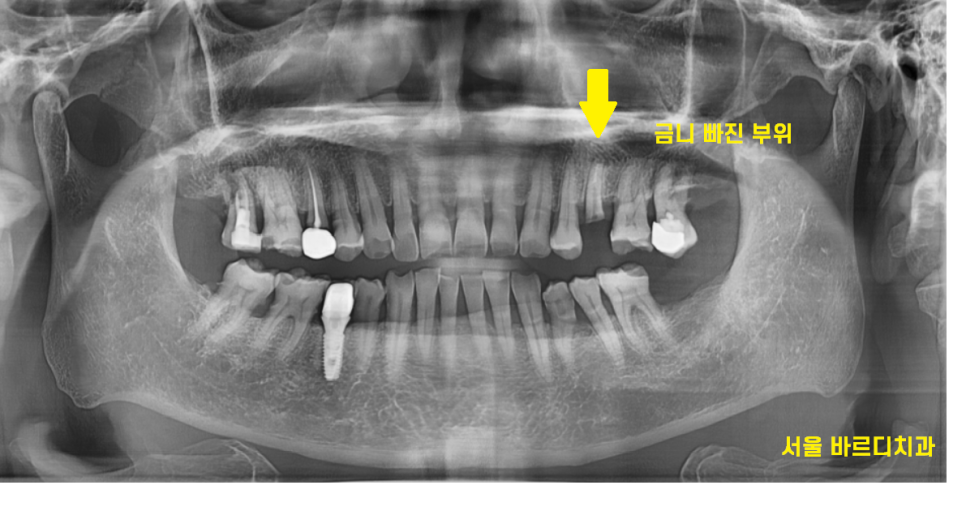

오래전 하셨던 금니 보철물이 빠져

내원한 환자분입니다.

23.11.01

금니 빠짐 부위가 치아와 함께

부러졌네요ㅠㅠ